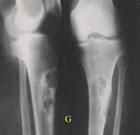

1.骨化性纖維瘤:主要由纖維母細胞組成,骨樣組織和骨小梁僅占腫瘤小部分,故X線片上呈輪廓清晰的密度減低區,有時呈圓形、卵圓形或不規則的房室,其中有不整齊的粗糙骨隔,皮質骨變薄和膨脹,鄰牙移位。

2.纖維骨瘤:以骨質為主,有不同形式的骨小梁,並逐漸鈣化,故X線片上呈較緻密影響,伴不規則團塊狀骨化或鈣化,亦可見骨小梁結構,多從牙槽嵴處開始。